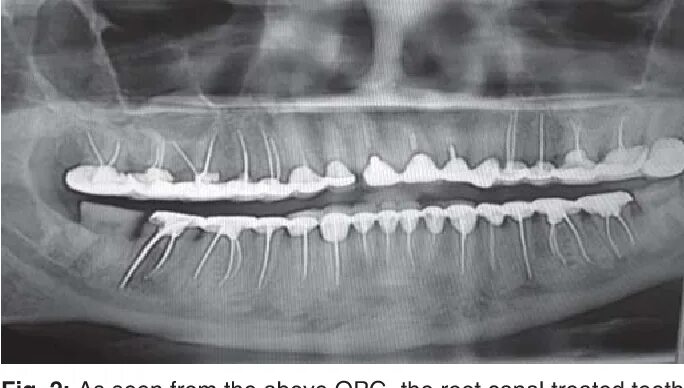

Зубы штифты можно ли делать мрт